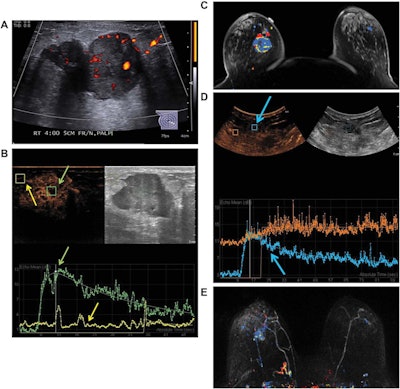

Images are from a 50-year-old woman presenting with a right breast lump that has biopsy-proven infiltrating ductal carcinoma. A: Targeted right-breast ultrasound imaging showed an oval hypoechoic mass with indistinct margins measuring up to 3.7 cm. B: At baseline before starting neoadjuvant chemotherapy, CEUS showed an avidly enhancing tumor (green arrows) with tumor peak intensity on the time-intensity curve generated by the Qlab software. The region of interest was placed on adjacent normal breast tissue (yellow arrows), which had a flat line on the time-intensity curve. The y-axis of the time-intensity graph corresponds to the intensity or mean echo (decibels), whereas the x-axis corresponds to the absolute time (seconds). C: Axial postcontrast fat-saturated MRI at baseline showed an enhancing tumor with mixed kinetics in the right breast. After neoadjuvant chemotherapy was completed but before surgery, contrast-enhanced and MRI scans were again performed. D: CEUS showed a 2-cm residual enhancing tumor with a time-intensity curve (blue arrows) that had rapid enhancement and washout. E: Maximum-intensity projection contrast-enhanced MRI performed after neoadjuvant chemotherapy was completed showed a decrease in the size of tumor to 2 cm with predominantly progressive kinetics. At the time of right lumpectomy, this patient had 1.5 cm of invasive tumor in the right breast, consistent with a noncomplete pathologic response. Both the contrast-enhanced ultrasound and MRI studies predicted that there would be noncomplete pathologic response at the time of surgery. Images courtesy of the Journal of Ultrasound in Medicine.